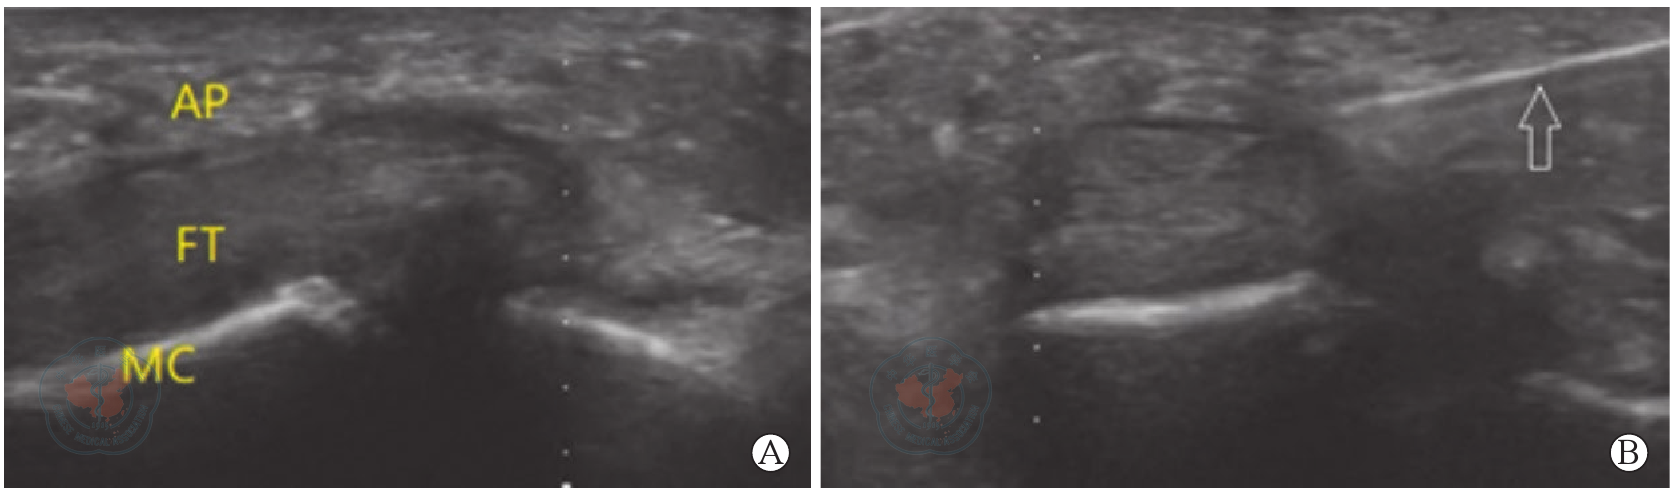

图3 超声下掌指关节部位结构。图A为超声下近端掌指关节部位,结构清晰可见;图B示超声下针的形态(白色箭头)注:MC-掌骨;FT-屈肌腱;AP-A1滑车

Figure 3 Ultrasound anatomy of the metacarpophalangeal joint. A is proximal metacarpophalangeal joint, showing clearly the joint structure; B shows needle appearance under ultrasound view (white arrow)Note: MC-metacarpal;FT-flexor tendon;AP-A1 pulley